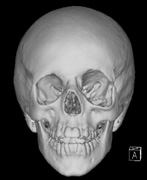

Growth of a plexiform neuroma may be directed posteriorly, infiltrating orbital tissues and involving the bony walls. Congenital plexiform neuromas of the orbit are often associated with absence of the sphenoid wing (Fig. 5). Intracranial pulsation can be transmitted to the orbit causing pulsatile proptosis or enophthalmos.57–59 Plexiform neuromas of the lid and orbit are difficult to treat; complete excision is difficult and potentially disfiguring. The tumors are vascular and may bleed copiously at surgery. They are not radiosensitive and there is also risk of inducing malignant transformation. Trials with antiangiogenic chemotherapeutic agents (thalidomide, interferon alpha) and mitotic-signaling pathway blockers (inhibition of Ras by Farnesyl protein tranferase inhibitor) are in progress.60,61

Fig. 5. Surveillance images from a 15-year-old boy with a history of visual loss, proptosis and a diagnosis of NF1. Postcontrast axial (a) and sagittal (b) T1-weighted images demonstrate a plexiform neurofibroma of the left upper and lower eyelids, which extends into the orbit and to the extraconal soft tissues through a widened superior orbital foramen, best seen in (c). An optic nerve glioma widens the optic canal. (d) A sphenoid wing dysplasia is visible and seen as asymmetry of the orbits on the 3D CT bone reconstruction images.